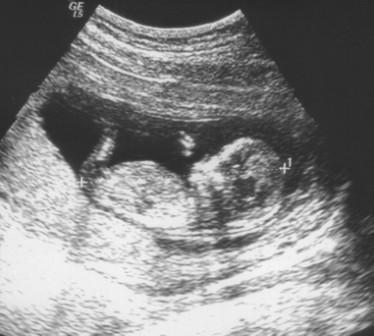

Hallo! Hatte heute FA Termin mit Nackenfaltenmessung, und zum Glück kann ich positive Nachrichten berichten.. Das Baby ist super gewachsen und nun 6,5 cm gross, hat sich viel bewegt und gestrampelt! Nackenfalte war bei 1,7mm und das ergibt für mich ein Risiko von 1:2700... also auch ganz gut ausgefallen.. leider hat mich nur wieder die Übelkeit eingeholt und ich musste mich sogar dort übergeben :-( Naja, bin einfach nur erleichtert & heilfroh dass alles gut ist, ich hatte schon so viele Sorgen durch die vielen so traurigen Berichte hier im Forum! alles Liebe & einen schönen Abend, Majabienchen